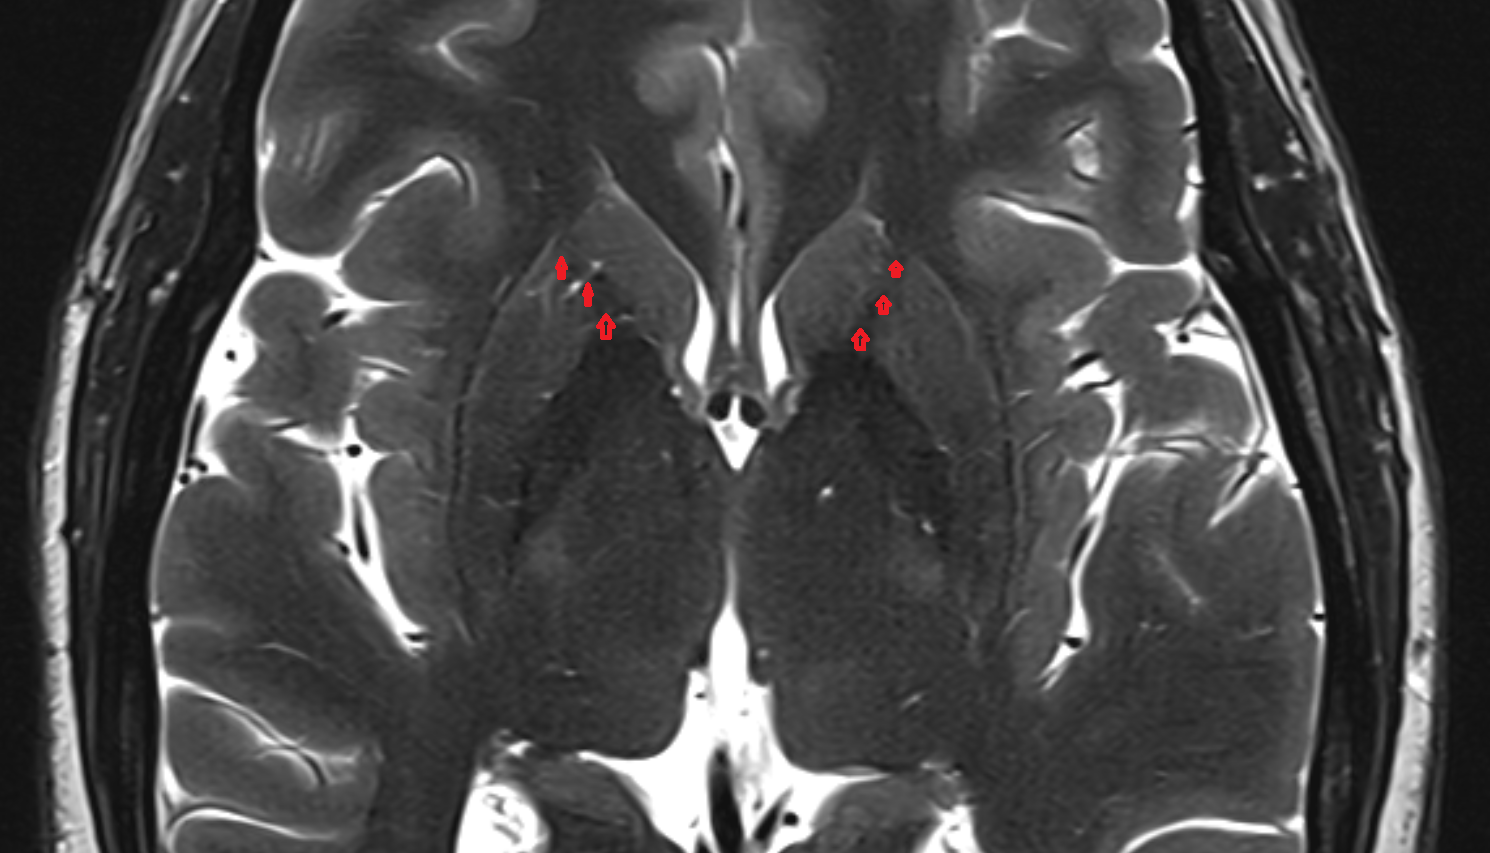

- Hippocampal body

- Hippocampal head

- Hippocampal tail

- Body of hippocampus

- Head of hippocampus

- Tail of hippocampus

- Hippocampus